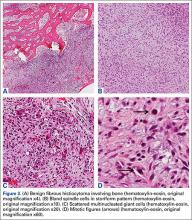

Grossly, the tumor was pale tan and firm. Histologic examination with hematoxylin-eosin staining revealed a bland spindle-cell neoplasm that focally involved bone. A storiform pattern was present. The cells had scant cytoplasm and oval to elongate nuclei with tapered ends. Significant nuclear pleomorphism was not seen. The stroma was loose, with focal myxoid change. Benign multinucleated giant cells were present. Mitotic activity was infrequent (Figures 3A–3D). Two attending pathologists reviewed the case material and the frozen and formalin-fixed specimens independently and concurred with the diagnosis of BFH. In addition, the case was reviewed at the surgical pathology consensus conference; the reviewers agreed on BFH, and additional studies were deemed unnecessary.